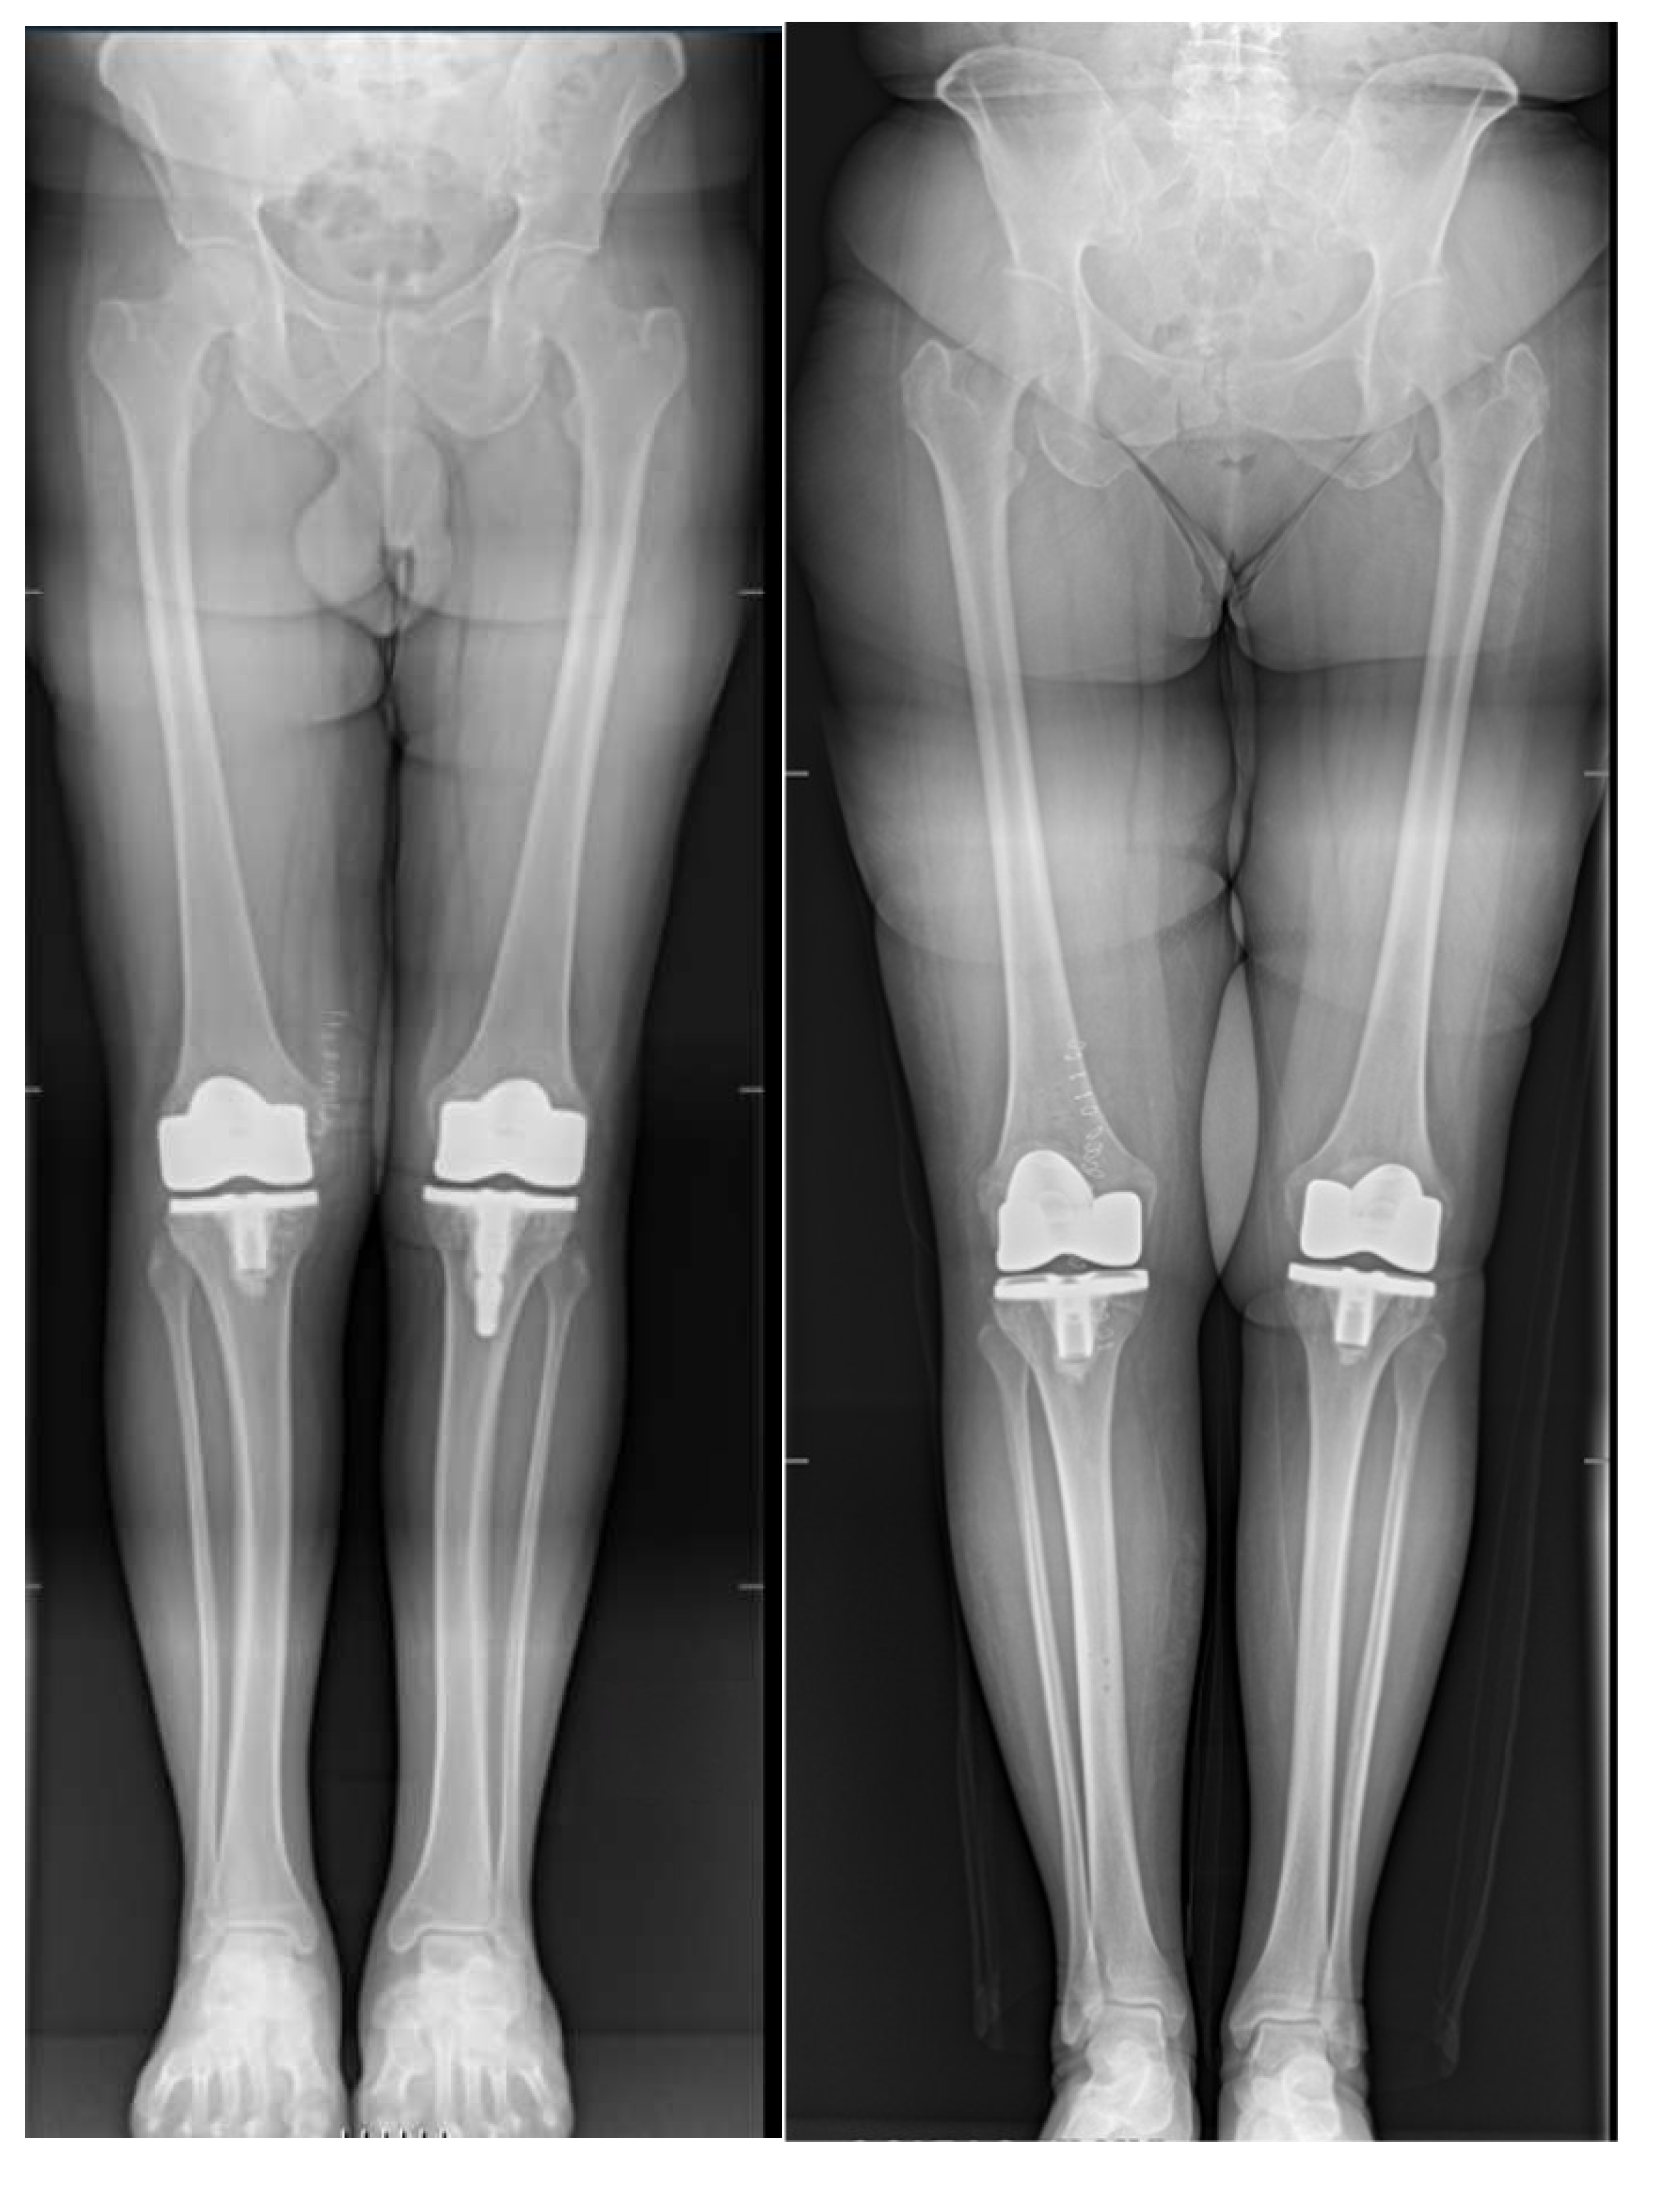

According to limitations previously highlighted [19], the planned intraoperative MPTA, LDFA, HKA, DFF, and TS angles of bone resections were extracted from the surgical report generated by the ROSA Knee System. Postoperative evaluation of radiographic outcomes was conducted three months postoperatively, and angle measurements were performed, as shown in Table 1. Standardized full-length weight-bearing anteroposterior lower limb radiographs and lateral 90° flexion knee and axial radiographs of the patella were obtained (Figure 1, Figure 2 and Figure 3). Incomplete radiographs because of a lack of weight bearing or incomplete extension warranted the exclusion from the present study. The arithmetic mean was calculated for each measurement performed by the two observers, and the obtained values were used for statistical purposes. Outliers from target angles were considered as follows: MPTA 90° ± 3°, LFDA 90° ± 3°, HKA 180° ± 3°, DFF 3° ± 3°, and TS 7° ± 3.

No significant differences were found between planned (robotic) and achieved (radiographic) results for femoral and tibial coronal angles and HKA (Table 4 and Figure 1).

Figure 1. Example of a full-length weight-bearing anteroposterior lower limb radiograph used for measurements.